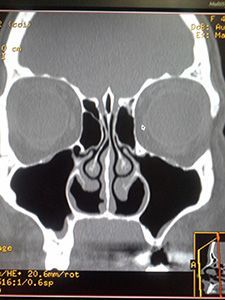

• Рентгенография околоносовых пазух – выявление затемнения в области пораженной пазухи;

• Компьютерная томография – при недостаточной информативности рентгенографии;